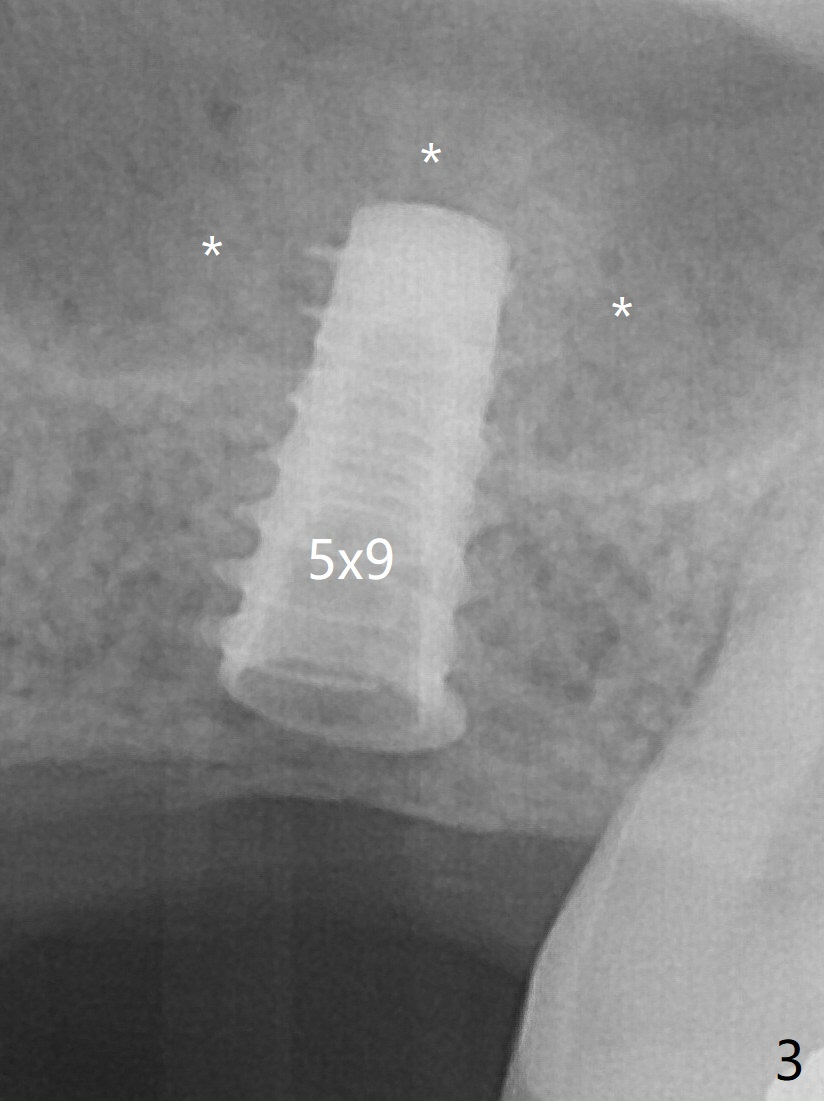

After insertion of a 4.5x11 mm dummy implant at 9 mm (35 Ncm; for further bone expansion), one piece of PRF plug and 1 piece of PRF membrane are pushed into the osteotomy, followed by allograft mixed with autogenous bone for sinus lift (*) and placement of a 5x9 mm implant (Fig.3,4 with insertion torque >50 Ncm). The implant appears to have been placed too deep. In fact a BW shows otherwise. There is mild bone resorption at the crest 11 months postop (Fig.7 *). Although the sinus lift with bone graft becomes less distinct, there is more implant/bone contact mesial (arrow). The bone resorption seems to be worse 8 months post cementation (Fig.8,9); in fact the abutment screw is loose. The gingiva is healthy.